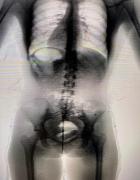

A ocorrência foi detectada por meio do equipamento Body Scan, utilizado no controle de acesso durante o horário de visitação. Por volta das 11h, durante inspeção na Galeria A, o equipamento apontou anormalidade, indicando indícios de possível ocultação interna de material ilícito.

Diante da fundada suspeita, a visitante foi encaminhada ao Hospital Regional de Irecê para realização de exame de imagem complementar (tomografia computadorizada), que confirmou a presença de corpo estranho em cavidade corporal.

Após orientação médica, a própria envolvida realizou, de forma voluntária, a retirada do material, sendo constatado aproximadamente 0,60 gramas de substância análoga à cocaína, acondicionada em invólucro específico para ocultação interna.